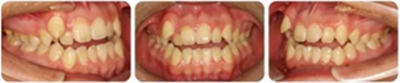

張某,男性,13歲,主訴前牙反頜伴開頜,要求矯治。

正面觀雙側(cè)基本對(duì)稱,垂直向基本協(xié)調(diào);側(cè)面觀直面型,下頜平面角較陡。顳下頜關(guān)節(jié)未見(jiàn)異常。

恒牙列,上中線右偏2mm,下中線左偏3mm,左側(cè)尖磨牙Ⅰ類 ,右側(cè)尖磨牙Ⅲ類。前牙反頜,13唇側(cè)低位萌出。上牙列擁擠度10mm,下牙列擁擠4mm。

(1)安氏Ⅲ類亞類錯(cuò)合;

(2)前牙開頜、反頜;

(3)13唇側(cè)低位萌出。